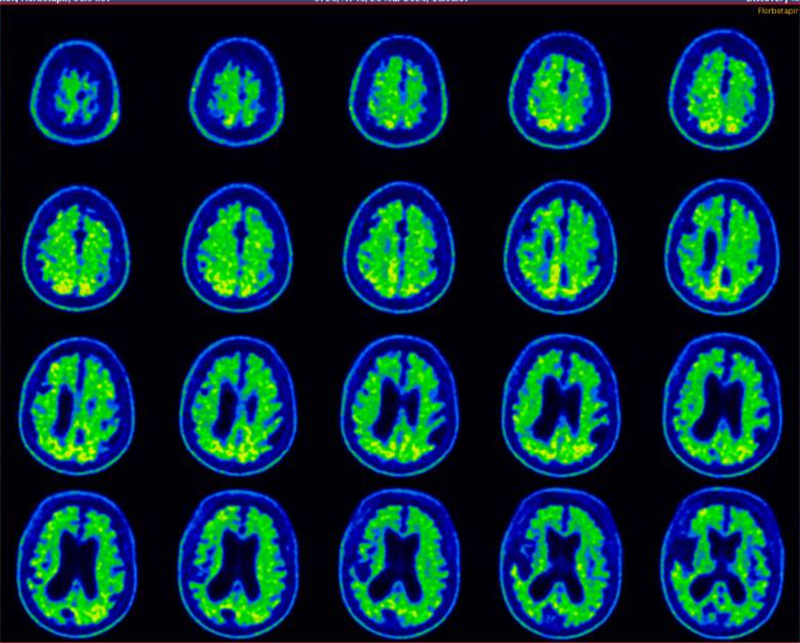

經(jīng)過PET-CT影像學(xué)評(píng)估、腦脊液生物標(biāo)志物檢測及多學(xué)科會(huì)診,醫(yī)院高級(jí)認(rèn)知障礙診療中心團(tuán)隊(duì)確認(rèn)患者雖屬重度阿爾茨海默病,但無嚴(yán)重基礎(chǔ)疾病,符合手術(shù)指征。